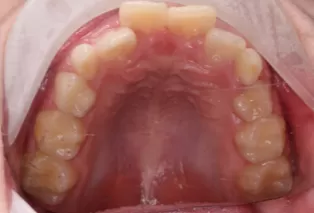

Intraoral photos